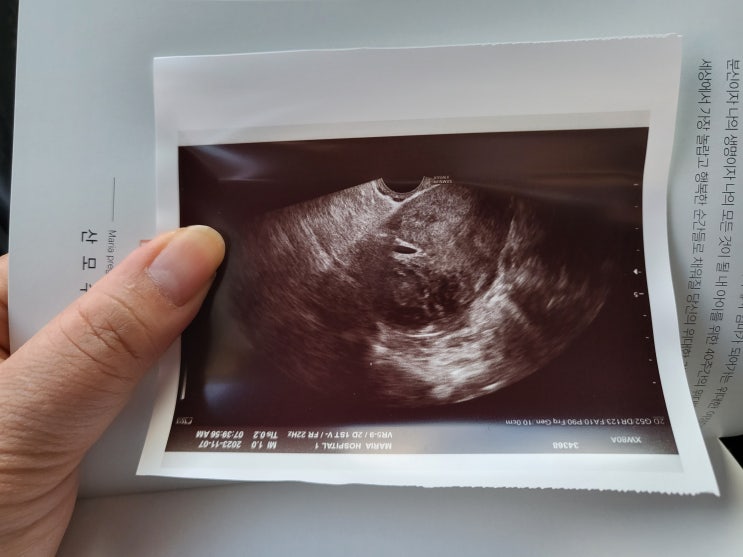

난임시술 3차, 방문5회, 임신 초음파검사, 임신피검사[상봉마리아에스,허창영원장님]

냉동배아 이식 (5일배아 1개) 임신 초음파,피검사 2023.11.7.화 임신 5주 1일 아침에 크리논겔 질정 유지 ...